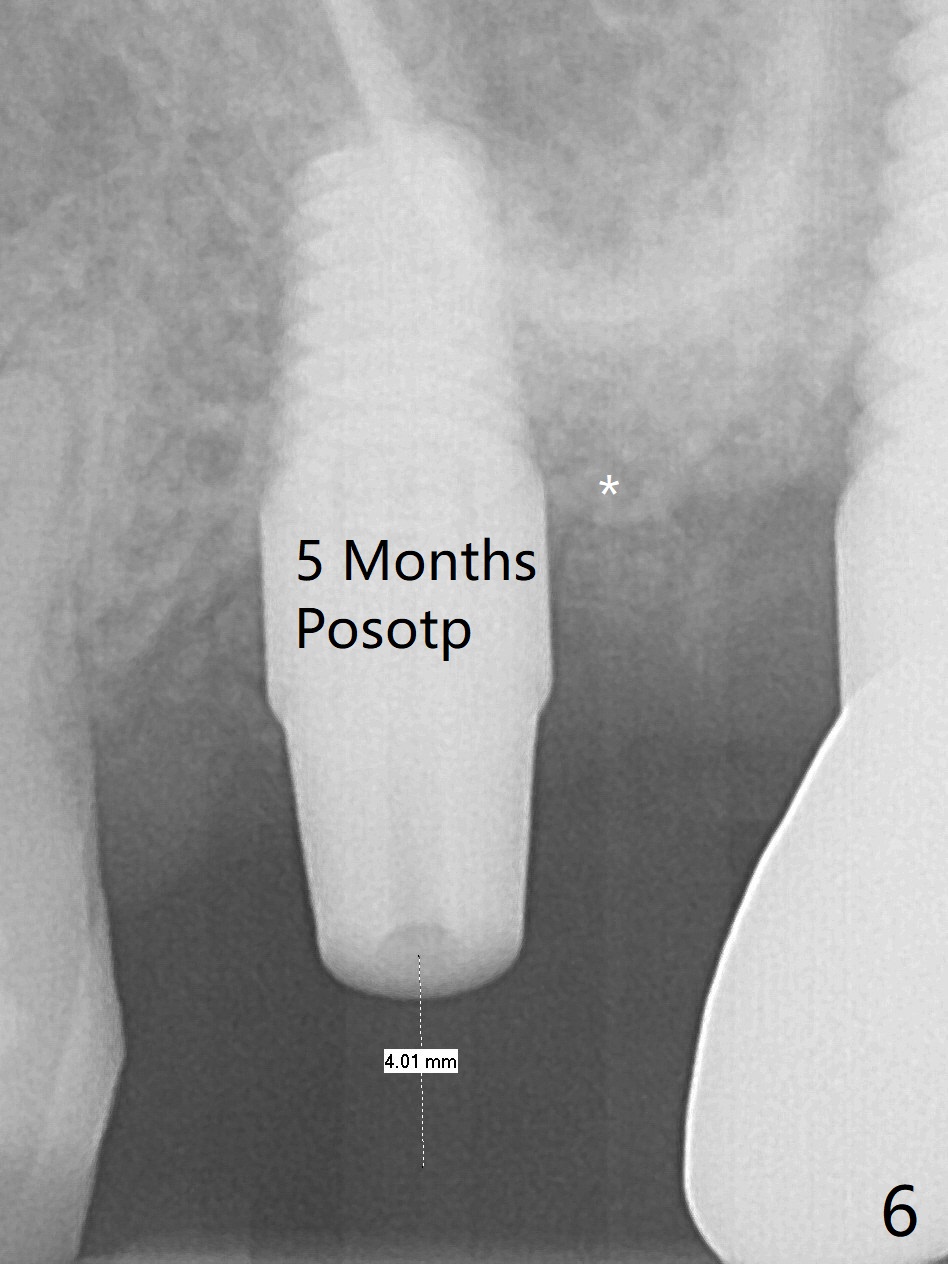

After osteotomy with guide at #14 (4.5x7.3 mm last drill with 1 O-ring/10.5 mm offset for bone-level implant), a 5x11 mm tissue-level tap is used with allograft for sinus lift (Fig.1). With one more round of allograft for sinus lift, a 5x11 mm tissue-level implant is placed with ~ 50 Ncm (Fig.2). CBCT 3-D images (Fig.3 (palatal view), 4 (distal view) (D: distal)) and coronal section (Fig.5 (P: palatal)) show the bone graft in the sinus (*). The patient returns for restoration 5 months postop in spite of running out insurance benefits because of discomfort with the immediate provisional. When the latter is removed (Fig.6), the gingiva is erythematous. It appears that the implant was placed deep. The abutment is removed for easy local oral hygiene. A healing cuff will be used or the implant will be reversely torqued. If the former is placed, a 4 mm longer abutment (4.5x9 mm) should be used to increase crown retention using temp bond . In fact the provisional forms a nice gingival cuff before cementation (Fig.7,8). Return to Upper Molar Immediate Implant, Prevent Molar Periimplantitis (Protocols, Table), Trajectory 18 Xin Wei, DDS, PhD, MS 1st edition 04/22/2019, last revision 02/28/2020